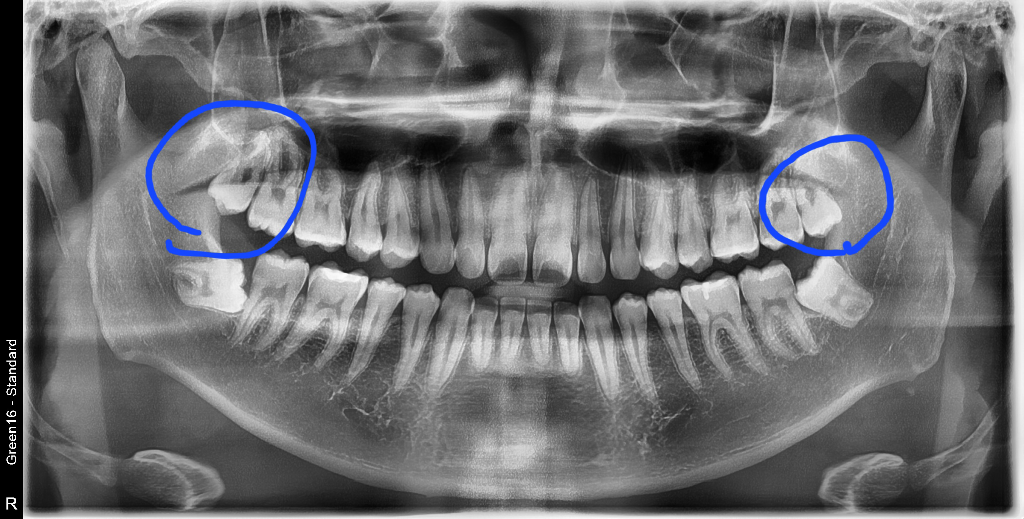

파랗게 그린쪽의 사랑니는 꼭 뽑으라고 원장님이 말씀하셔서 한달내로 예약잡고 발치하려는데, 저 사랑니는 다른케이스보다 뽑기 어려운가요? 완전매복이아니라 절개량이 적어 괜찮다는데 그럼 발치중,발치후 통증도 비교적 다른 케이스보단 덜할까요?

• 2번 째 사진

상악의 경우 사랑니 발치가 크게 난이도가 높은편은 아닙니다. 저정도면 쉬운편에 속할것같습니다.

사랑니 발치 난이도가 쉬운 편으로 보입니다. 위 사랑니이기도 하고, 대합도 되지 않아 고생을 많이 하지는 않으실 것으로 예상되나 항상 변수가 있을 수 있으니 너무 걱정하실 필요는 없으나 주치의 선생님 설명대로 잘 따라주세요.

두 사랑니 모두 어려워보이지는 않습니다. 발치 중, 후 통증이 모두 적은 편 일 것 같습니다.

네 일반사랑니이며 굳이 절개가 필요하지 않을 것 같습니다 최소한 침습적으로 처치하므로 술후 통증도 덜할것입니다